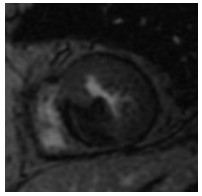

入院后签署患者知情同意告知书,查血常规、凝血谱、电解质、血生化、甲状腺功能、肿瘤标志物、C反应蛋白和脑钠肽均未见明显异常,心电图示窦性心律,顺钟向转位。连续心电遥控监护5 d未见明显室性心律失常。心脏超声和经食道心脏超声检查提示室间隔及左室下壁中段近后内侧乳头肌处可见一个偏高回声区,主要位于心肌内,浸润心肌全层,部分凸向左室腔,略见活动及变形,未累及二尖瓣和主动脉瓣,未见心腔流入道和流出道梗阻,未见明显心包积液。左心声学造影显示室间隔中下段偏强回声团块内未见明显血流信号,乏血供表现。心脏多层螺旋计算机断层扫描(CT)示室间隔内异常密度,测其CT值为-31.3 Hu,提示为脂肪组织密度,增强后病灶未见强化,诊断为脂肪来源肿瘤,脂肪瘤考虑(图 1~2)。心脏磁共振(CMRI)增强扫描示FIESTA序列显示后室间隔-左室下壁见一混杂高信号“小核桃”样大小肿物,T2WI(图 3)上为高信号,Triple IR序列(图 4)上病灶全部为低信号,提示为纯脂肪成分,病变周围可见低信号环,提示为化学位移伪影,病变质地较软,边界尚清楚,电影序列可见病灶柔软摆动,并随心动周期形态改变,局部突入左心室,舒张末期测量大小约25 mm×19 mm×36 mm,灌注序列见灌注确实,延迟增强未见强化,拟诊为心脏脂肪瘤(图 5)。SPECT心肌静息灌注显像见室间隔和左室下壁局部心肌血流灌注减低。18F-FDG PET-CT显像提示室间隔-左室下壁心肌内病变糖代谢减低,考虑为脂肪源性病变,全身未见局部异常密度增高。

| 图 4 心脏磁共振图(肿瘤在Triple IR序列上病灶全部为低信号,提示为纯脂肪成分) |

当发现存在心脏肿瘤时,首先需要明确其性质,尤其是良恶性。CT和磁共振对脂肪瘤的识别具有高度特异性[12-13],本患者CT检查示室间隔脂肪组织均匀低密度影。MR清晰显示肿瘤边界,T1W1呈强信号,T2W1呈稍强信号,脂肪组织序列呈弱信号,钆增强后也未见明显强化,对映证脂肪瘤均有较大价值。患者肿瘤的CT值同皮下脂肪组织,同时结合心超等其他影像学依据可排除黏液样变、血管组织、肌肉组织、纤维组织和错构瘤等其他组织来源,因此可临床确诊为脂肪来源的肿瘤。肿瘤形态、血供是否丰富和代谢是否活跃是鉴别脂肪瘤和脂肪肉瘤的重要依据。超声、CT和磁共振均提示肿瘤为单个,与周围组织边界清楚。患者接受了超声左心声学造影和核素心肌静息灌注显像检查,均提示肿瘤血供明显不丰富。18F-FDG PET-CT检查显示肿瘤放射性摄取呈稀疏缺损区,提示葡萄糖代谢减低,符合良性肿瘤表现,同时也未见全身其余部位有高糖代谢病灶,因此临床诊断良性脂肪瘤成立。2011年AECVP/SCVP心内膜心肌活检共识声明认为对左心系统肿瘤无需进一步进行心肌活检[7]。